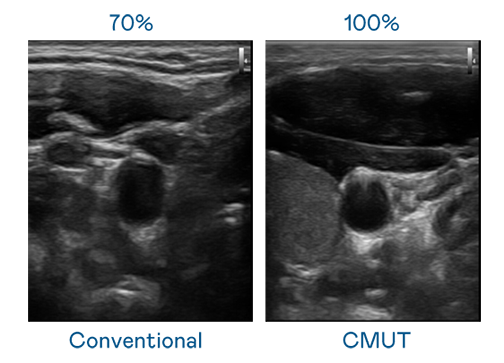

CMUT 技术是一种用电容式微机电元件来产生超音波讯号的技术。与传统 PZT 压电式技术相比,CMUT 频宽增加 30%,更宽频的超音波讯号让影像解析度大幅提升,是实现高影像品质医疗超音波扫描、促进精准医疗发展的关键技术。

大频宽带来超清晰影像

超音波影像的解析度高低,首先取决于探头能发出的讯号频宽。j9集团 CMUT 可提供高清晰的超音波讯号,提供高频宽、高灵敏度、影像纹理细节更高的超音波影像,协助医护人员缩短影像判读时间及利用精准的医疗影像进行诊断。